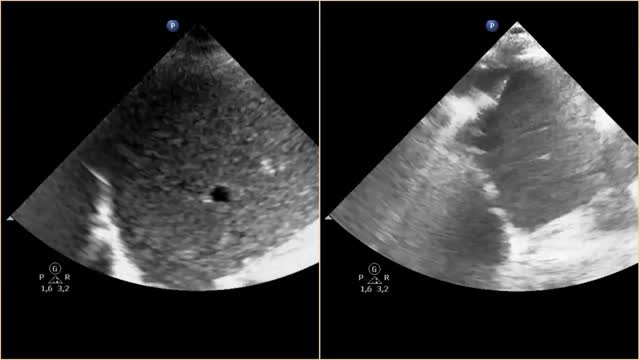

Paciente de 55 años que ingresa en la UCI tras cirugía cardiaca de reparación de comunicación interauricular tipo ostium secundum y drenaje venoso pulmonar anómalo. Tras la extubación, sin incidencias, permanece con hipoxemia sin alteraciones en la radiografía de tórax. Se realiza ecografía pulmonar en la que se objetiva una disminución del movimiento diafragmático derecho en comparación con el izquierdo (vídeo 1). Se mide la excursión diafragmática apreciándose una excursión derecha reducida de 16mm frente a una excursión izquierda de 60mm (fig. 1). Estos hallazgos son compatibles con parálisis diafragmática derecha en relación con una probable lesión del nervio frénico ipsilateral durante la cirugía. Mediante manejo conservador con fisioterapia respiratoria incentivada, la paciente evoluciona favorablemente hasta el alta, aunque con persistencia de la disfunción diafragmática por ecografía.